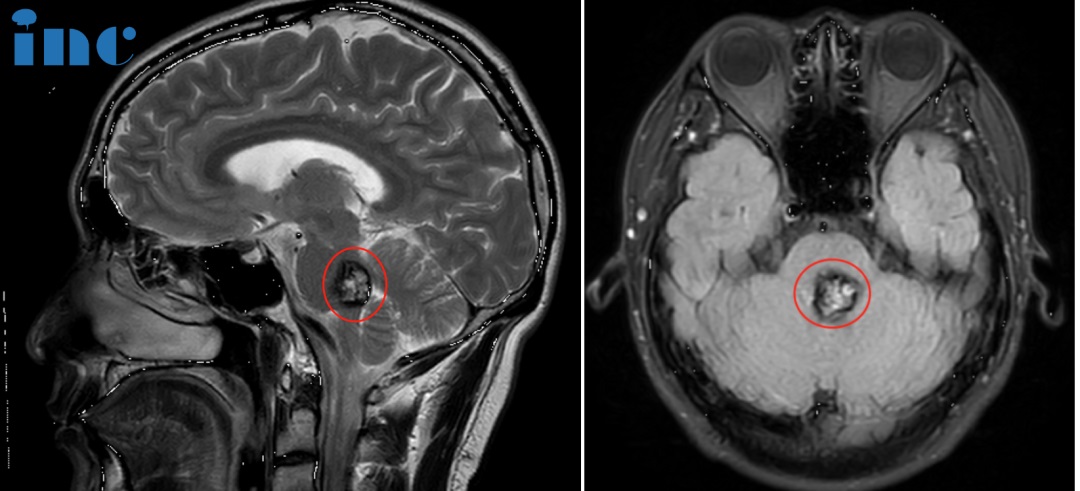

咨詢(xún)室迎來(lái)2位患者,30歲的萱萱2023年3月查出中腦及橋腦右側(cè)占位海綿狀血管瘤繼發(fā)出血。當(dāng)?shù)蒯t(yī)生考慮手術(shù)風(fēng)險(xiǎn)大,偏癱幾率大,建議保守治療。和很多年輕的腦干海綿狀血管瘤女性患者一樣,當(dāng)她們步入婚姻自然的要迎接新的小生命。但這一直虎視眈眈的腦干海綿狀血管瘤一旦伺機(jī)而動(dòng)如出現(xiàn)急性腦干出血,而致患者和胎兒于困境中,又該怎么辦?

萱萱多方打聽(tīng)之后,了解到在腦干海綿狀血管瘤治療領(lǐng)域一位國(guó)際神外教授巴特朗菲教授,專(zhuān)門(mén)研究過(guò)孕期海綿狀血管瘤的治療。通過(guò)INC他們遠(yuǎn)程咨詢(xún)巴教授,巴教授表示這是一個(gè)潛在的手術(shù)病例,因?yàn)橛邢喈?dāng)大的內(nèi)出血。然而,手術(shù)指征需仔細(xì)地被確定,因?yàn)檫@名年輕患者的臨床狀況好。我們較好在近期與患者單獨(dú)面談,詳細(xì)討論此事。得到巴教授的回復(fù)之后,他們決定再一次親自見(jiàn)見(jiàn)巴教授,完全解決這個(gè)“不定時(shí)炸彈”。

詳細(xì)問(wèn)診、審閱各種影像資料后,巴教授說(shuō)道:“我有很多病人都患有這種畸形。通常,出過(guò)一次血,將來(lái)發(fā)生出血的可能性很高。而且這個(gè)畸形也不太小,至少有2厘米。這意味著,我們不能指望它可以一直保守下去。另一點(diǎn)是,如果你想要一個(gè)孩子,那么出血的風(fēng)險(xiǎn)也很高。這是眾所周知的,這是因?yàn)閼言泻蟮募に?。與正常情況相比,血液中的懷孕激素會(huì)增加更大的可能性。其中一些病變的表面有一個(gè)黃體酮的受體。黃體酮會(huì)導(dǎo)致新的出血。目前也沒(méi)有藥物可以治療這個(gè)疾病,因此只能手術(shù)。這種手術(shù)是我的專(zhuān)長(zhǎng)。我做過(guò)很多這樣的手術(shù),結(jié)果很好,沒(méi)有長(zhǎng)期性的問(wèn)題。我在獨(dú)墅湖醫(yī)院做了很多手術(shù),他們這里有很好的設(shè)施。切除率全切在海綿狀瘤中,這是可能的。”